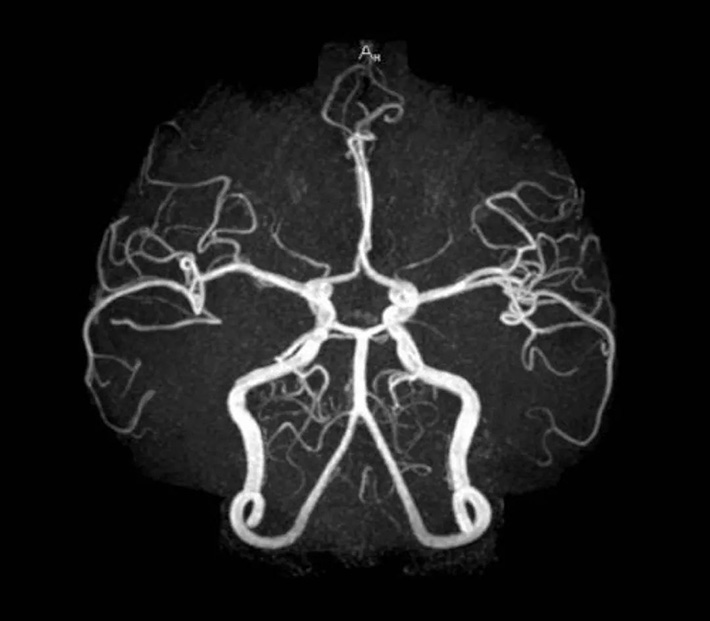

resonancia magnética nuclear

Sensible al diagnóstico temprano, puede mostrar anomalías en las primeras etapas de algunas lesiones y puede detectar problemas antes que los métodos de TC y ultrasonido B. Es más adecuado para exámenes de la cabeza, médula espinal, huesos, extremidades, etc. Por lo tanto, es especialmente efectivo para el examen de la base del cráneo y el canal espinal. En comparación con la TC, también compensa el defecto de que no puede ser directamente una imagen multiplanar. La angiografía se puede formar sin inyección de agente de contraste, y la lesión se puede mostrar más claramente.

Desventajas: el método de imagen es complicado, el precio es relativamente más alto y generalmente no es la primera opción para el diagnóstico de enfermedades; dado que el equipo de emergencia no puede ingresar a la sala de resonancia magnética, este examen generalmente no es adecuado para pacientes particularmente críticos; La resonancia magnética no es buena para el feto, por lo que las mujeres embarazadas no pueden usarla. Esta prueba también está contraindicada en pacientes con implantes metálicos (p. ej., marcapasos, ciertos stents) en el cuerpo; La resonancia magnética muestra una calidad de imagen deficiente de las lesiones calcificadas y la piel ósea y, por lo tanto, no es adecuada para el diagnóstico por imágenes de fracturas y otras afecciones.